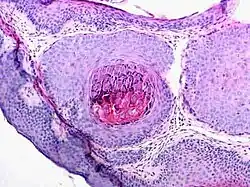

Microscopie

Le molluscum contagiosum réalise une lésion épidermique cratériforme. L'épiderme est épaissi et s'invagine en formant une masse volumineuse constituée de lobules piriformes convergeant vers un puits central[8]. Ces lobules sont constitués de cellules malpighiennes qui contiennent des corps molluscaires basophiles. De la périphérie vers le centre, les cellules perdent leur noyau, deviennent volumineuses, ovoïdes avec un cytoplasme fortement éosinophile devenant basophile. Cet aspect très caractéristique est dû à l'effet pathogène d'un poxviridé. En fonction des incidences de coupe, seules des masses dermiques sans connexion avec l'épiderme peuvent être visibles et ne doivent pas être confondues avec une tumeur.